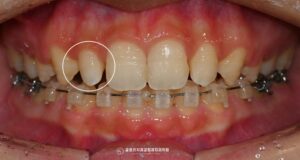

심하게 삐뚤어진 치열, 망우역 교정치과 에서 발치교정이 필요한 이유를 알려드립니다.

안녕하세요? 망우역 교정치과 김정은 원장입니다 :) 혹시 거울을 볼 때마다 삐뚤빼뚤한 치아가 신경 쓰이셨나요? 23.10.28 치열이 고르지 못한 것은 단순히 외관상의 문제만이 아닙니다. 치열이 고르지 못하면 발생하는 문제 ? 다음과…